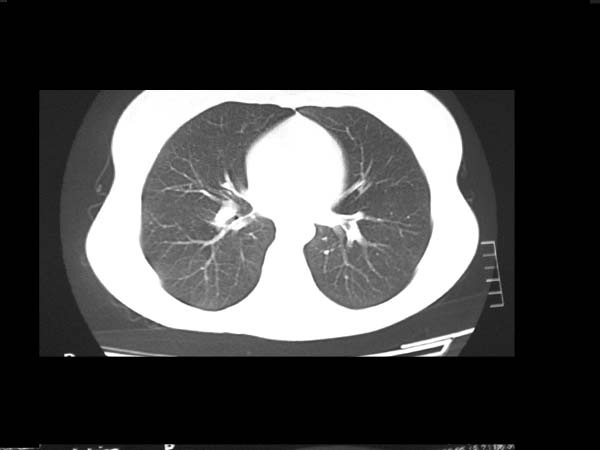

标题: CT13486:F 17Y 咳嗽 咳痰数日请会诊 [打印本页]

标题: CT13486:F 17Y 咳嗽 咳痰数日请会诊

白细胞9600不发烧

考虑右下结核球

右肺下叶结核灶

右下肺背段病灶,考虑结核与炎症鉴别,请进一步检查.

考虑结核球,建议治疗后复查

右下肺外基段病灶,考虑炎症,建议治疗后复查,以排外结核

考虑为:右肺下叶外基底段结核球。

结果;痰中找到结核杆菌

痰涂片已找到结核杆菌  将结果告诉大家